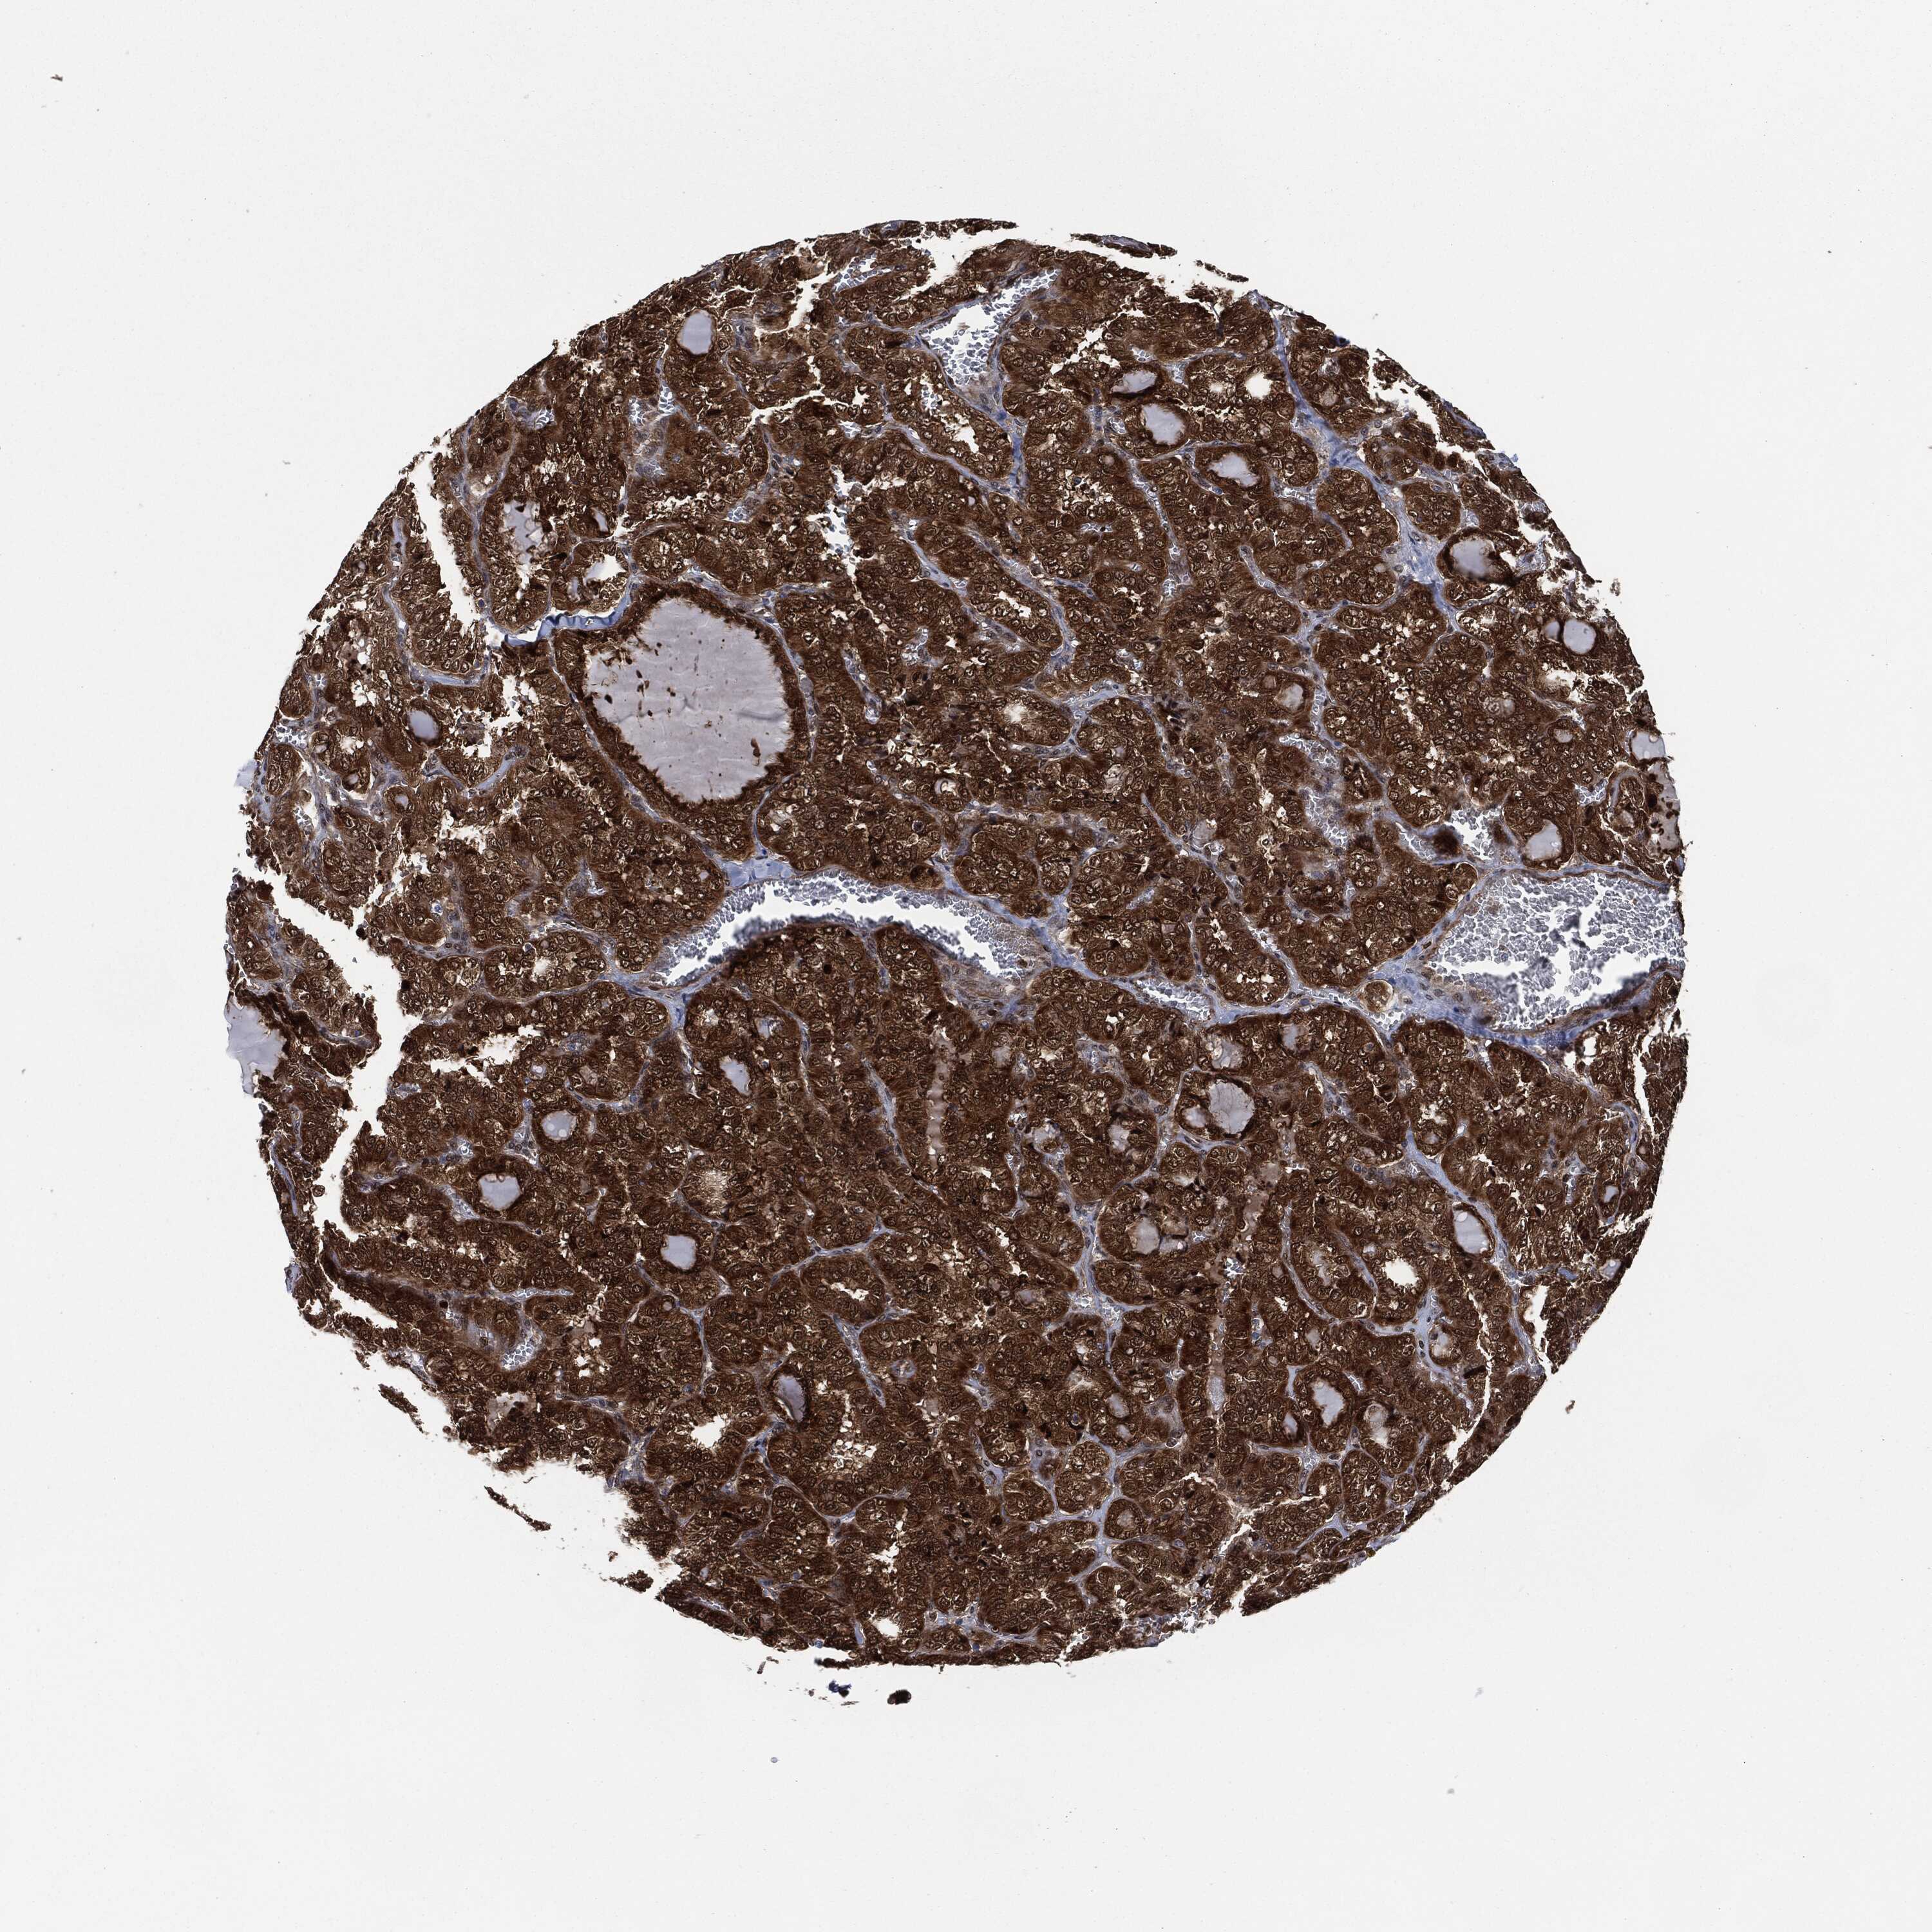

THYROID CANCER - Protein expressioni

A mouse-over function shows sample information and annotation data. Click on an image to view it in a full screen mode. Samples can be filtered based on level of antibody staining by selecting one or several of the following categories: high, medium, low and not detected. The assay and annotation is described here.

Note that samples used for immunohistochemistry by the Human Protein Atlas do not correspond to samples in the TCGA dataset.

Antibody stainingi

Antibody staining in the annotated cell types in the current human tissue is reported as not detected, low, medium, or high, based on conventional immunohistochemistry profiling in selected tissues. This score is based on the combination of the staining intensity and fraction of stained cells.

Each image is clickable and will lead to virtual microscopy that enables deeper exploration of all samples and also displays staining intensity scores, fraction scores and subcellular localization as well as patient and tissue information for each sample.

Antibody HPA034635

Antibody HPA069977

Antibody HPA071875

Antibody CAB009108

Staining

High

Medium

Low

Not detected

Intensity

Strong

Moderate

Weak

Negative

Quantity

>75%

75%-25%

<25%

None

Location

Nuclear

Cytoplasmic/membranous

Cytoplasmic/membranous,nuclear

Papillary adenocarcinoma, NOS

Follicular adenoma carcinoma, NOS